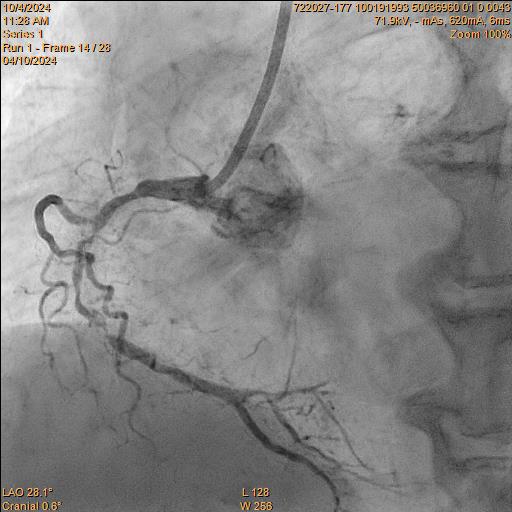

Pulmonary ArteriographyPA Pressure 55/26/36 mmHg. Pulmonary Arteriogram: Massive filling defect at main pulmonary trunk and bilateral pulmonary arteries (PA).Successful mechanical thrombectomy was performed under VA-ECMO Coronary AngiogramLMS: Mild diseaseLAD: Occluded from pLAD segment onward, retrograde from right systemLCx: Co-dominant, diffuse disease, critical stenosis at mLCxRCA: Co-dominant, mRCA critical stenosis, retrograde to LAD

Intervention of RCA Right Coronary Artery was engaged with JR 7Fr Guiding Catheter. Lesion was successful wired with Fielder XT-R and was changed back to workhorse (NS Runthrough) wire. Sequential predilatation using 1.0/15 Sapphire, 1.5/15 Sapphire II Pro, and 2.25/15 Sapphire II Pro was then carried out with Guideplus II assistance; unfortunately, severe balloon underexpansion was noted. Rotational Atherectomy (RA) was attempted 1.25mm Burr for 2 passes at 180k rpm. Lesion was further prepared with 3.0/13 NSE Aperta and 3.0/10 NC Sapphire 24 under Intra-vascular ultrasound (IVUS) guidance before deploying overlapping 3.0/40 Orsiro Mission, 3.5/40 Orsiro Mission and 4.0/18 Orsiro Mission. Repeat IVUS after stent optimization showed stent underexpansion. Hence, intravascular lithrotripsy (IVL) was performed with Shockwave 3.5/12 for a total of 80 shocks, followed by 3.0/10 NC Sapphire stent optimization.

Intervention of RCA Right Coronary Artery was engaged with JR 7Fr Guiding Catheter. Lesion was successful wired with Fielder XT-R and was changed back to workhorse (NS Runthrough) wire. Sequential predilatation using 1.0/15 Sapphire, 1.5/15 Sapphire II Pro, and 2.25/15 Sapphire II Pro was then carried out with Guideplus II assistance; unfortunately, severe balloon underexpansion was noted. Rotational Atherectomy (RA) was attempted 1.25mm Burr for 2 passes at 180k rpm. Lesion was further prepared with 3.0/13 NSE Aperta and 3.0/10 NC Sapphire 24 under Intra-vascular ultrasound (IVUS) guidance before deploying overlapping 3.0/40 Orsiro Mission, 3.5/40 Orsiro Mission and 4.0/18 Orsiro Mission. Repeat IVUS after stent optimization showed stent underexpansion. Hence, intravascular lithrotripsy (IVL) was performed with Shockwave 3.5/12 for a total of 80 shocks, followed by 3.0/10 NC Sapphire stent optimization.